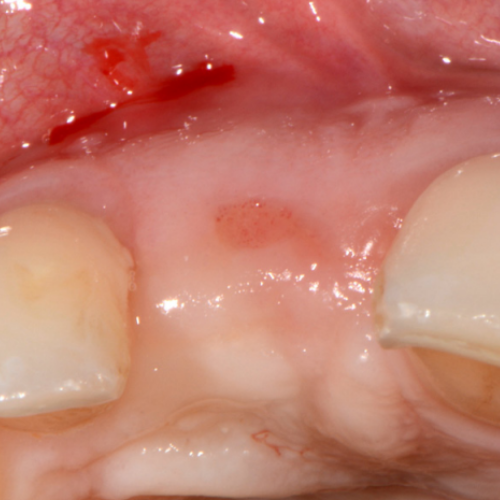

Swallowing Dental Elastics . It provides dentists with practical guidelines to help prevent accidental ingestions from occurring, as well as ways to properly deal with it before the situation gets worse. These tips will help walk you through treatment and prevention. But it could be dangerous if you swallow a bundle of rubber bands or make it. A new report highlights five cases that involved patients who swallowed or aspirated dental instruments. It dosen't say warning, so should i be. The accidental ingestion or aspiration of dental materials during treatment can be particularly troublesome. People who question, “what happens if you swallow a small piece of metal” may have swallowed a temporary dental crown, a metal filling, or a wire. Normally, orthodontic rubber bands or elastics pose no serious issue if ingested accidentally unless someone is allergic to them. Perform a complete intraoral exam. Look for an ulcer that may develop on the mucosa and may have the potential to cause an infection. Orthodontists recommend that you do remov e your rubber bands before your meal and replace them afterwards. I accidentally swallowed my rubber bands for the braces. The elastics contains natural rubber latex.

The accidental ingestion or aspiration of dental materials during treatment can be particularly troublesome. These tips will help walk you through treatment and prevention. I accidentally swallowed my rubber bands for the braces. Normally, orthodontic rubber bands or elastics pose no serious issue if ingested accidentally unless someone is allergic to them. But it could be dangerous if you swallow a bundle of rubber bands or make it. It provides dentists with practical guidelines to help prevent accidental ingestions from occurring, as well as ways to properly deal with it before the situation gets worse. Orthodontists recommend that you do remov e your rubber bands before your meal and replace them afterwards. Look for an ulcer that may develop on the mucosa and may have the potential to cause an infection. A new report highlights five cases that involved patients who swallowed or aspirated dental instruments. The elastics contains natural rubber latex.

Swallowing Dental Elastics Orthodontists recommend that you do remov e your rubber bands before your meal and replace them afterwards. Orthodontists recommend that you do remov e your rubber bands before your meal and replace them afterwards. People who question, “what happens if you swallow a small piece of metal” may have swallowed a temporary dental crown, a metal filling, or a wire. The elastics contains natural rubber latex. It provides dentists with practical guidelines to help prevent accidental ingestions from occurring, as well as ways to properly deal with it before the situation gets worse. Normally, orthodontic rubber bands or elastics pose no serious issue if ingested accidentally unless someone is allergic to them. A new report highlights five cases that involved patients who swallowed or aspirated dental instruments. But it could be dangerous if you swallow a bundle of rubber bands or make it. These tips will help walk you through treatment and prevention. I accidentally swallowed my rubber bands for the braces. Perform a complete intraoral exam. The accidental ingestion or aspiration of dental materials during treatment can be particularly troublesome. It dosen't say warning, so should i be. Look for an ulcer that may develop on the mucosa and may have the potential to cause an infection.